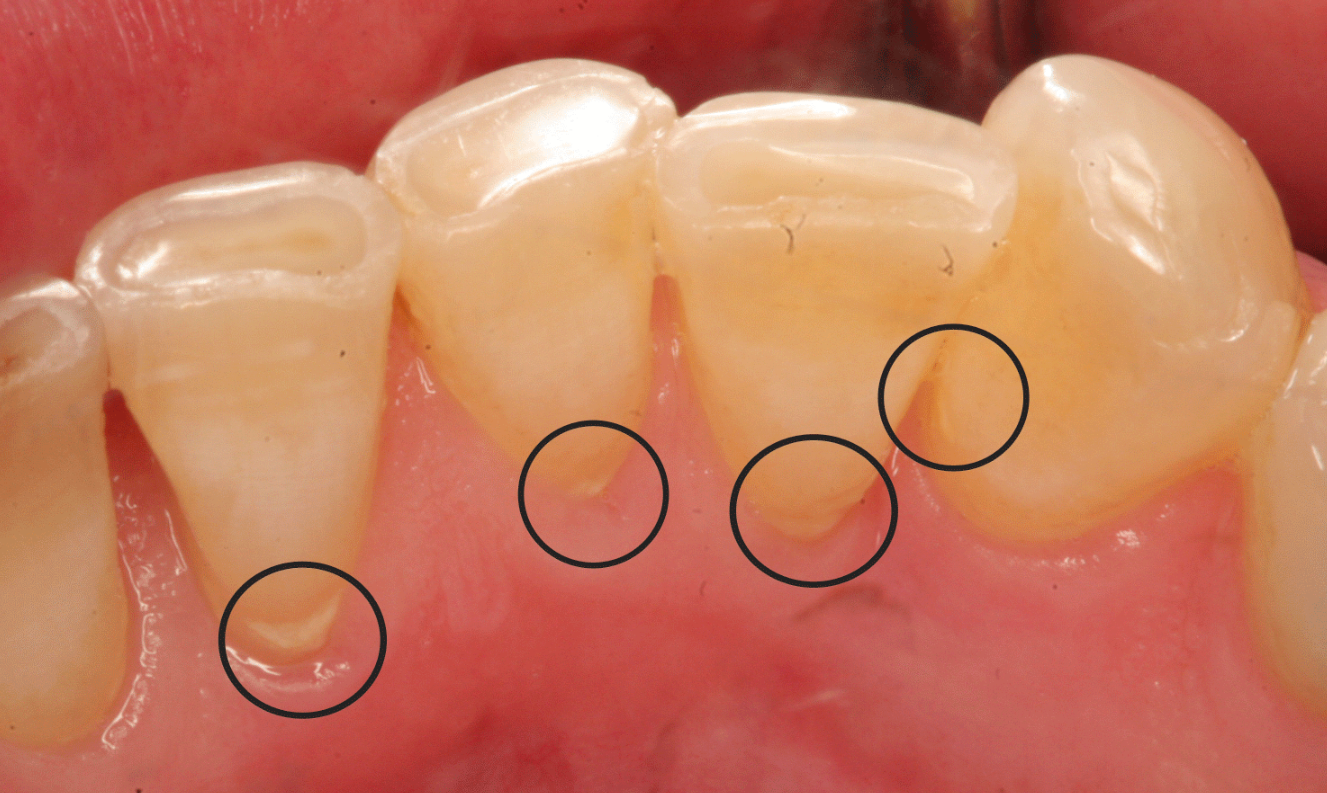

Hành động ăn nhai hàng ngày có ảnh hưởng trực tiếp đến răng. Nếu không chăm sóc và vệ sinh răng miệng đúng cách, có thể dẫn đến cao răng, mảng bám, sâu răng, viêm nướu và nhiều vấn đề nha khoa khác.

Khám nha khoa tổng quát giúp phát hiện sớm các vấn đề về răng miệng, từ đó có thể can thiệp điều trị kịp thời, tránh tình trạng bệnh lý hoặc các vấn đề nha khoa nghiêm trọng hơn. Việc phát hiện sớm trong quá trình khám tổng quát cũng giúp điều trị nhanh chóng và hiệu quả hơn.